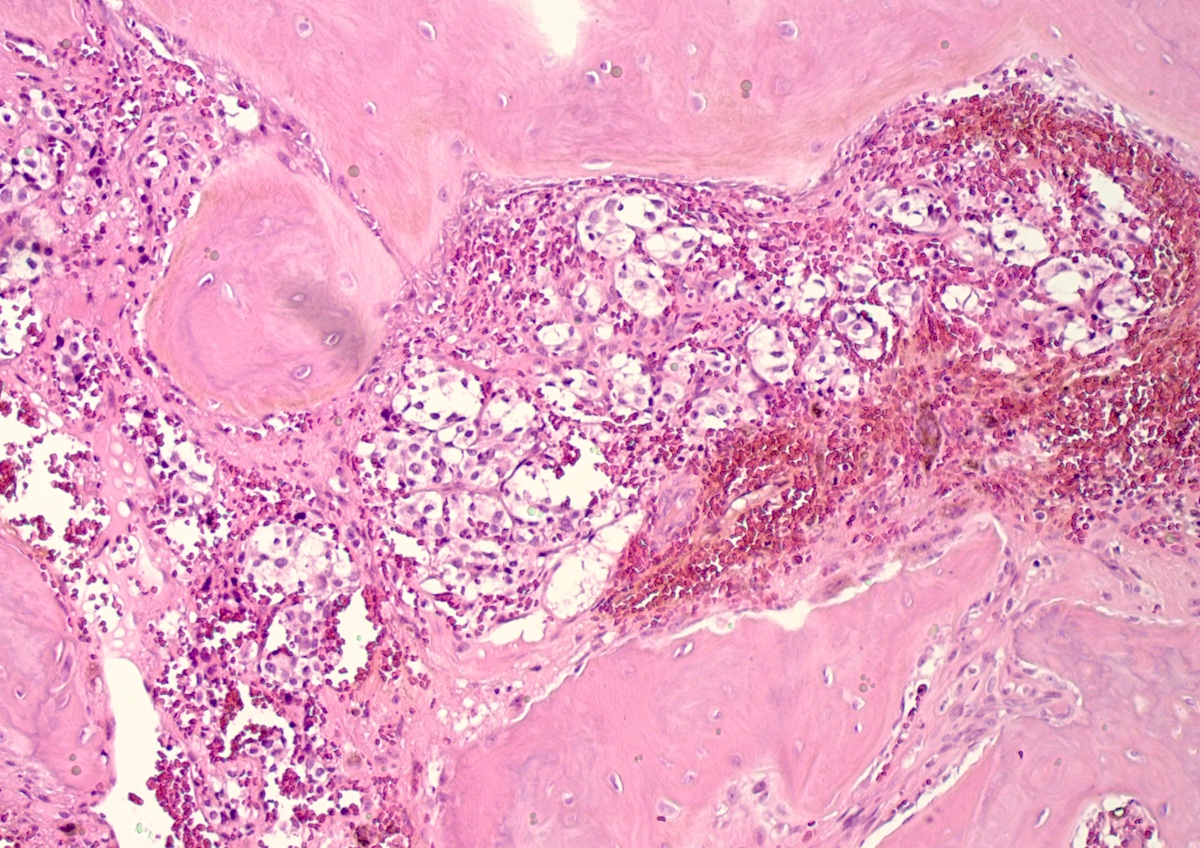

Microscopic (histologic) description

- Prevailing histologic pattern: epithelioid chief cells arranged in distinctive clusters / nests (zellballen pattern), separated by prominent fibrovascular stroma (J Clin Med 2018;7:280)

- Other patterns: pseudorosette, angioma-like, spindled and sclerosing

- Chief cells: round, oval to polygonal cells with abundant granular basophilic, eosinophilic or amphophilic cytoplasm (Surg Pathol Clin 2019;12:951)

- Intracytoplasmic hyaline globules may be present in sympathoadrenal paragangliomas

- Giant multinucleated cells and bizarre cells can be present (Srp Arh Celok Lek 2002;130:7)

- May have dysmorphic vessels, melanin-like pigment (neuromelanin) (pigmented paraganglioma), amyloid, abundant stroma and osseous metaplasia (Diagn Pathol 2012;7:77, Hum Pathol 1992;23:33)

- Necrosis is unusual except in patients who have undergone preoperative tumor embolization

Microscopic (histologic) images

Contributed by Luvy Delfin, M.D. and Sylvia L. Asa, M.D., Ph.D.